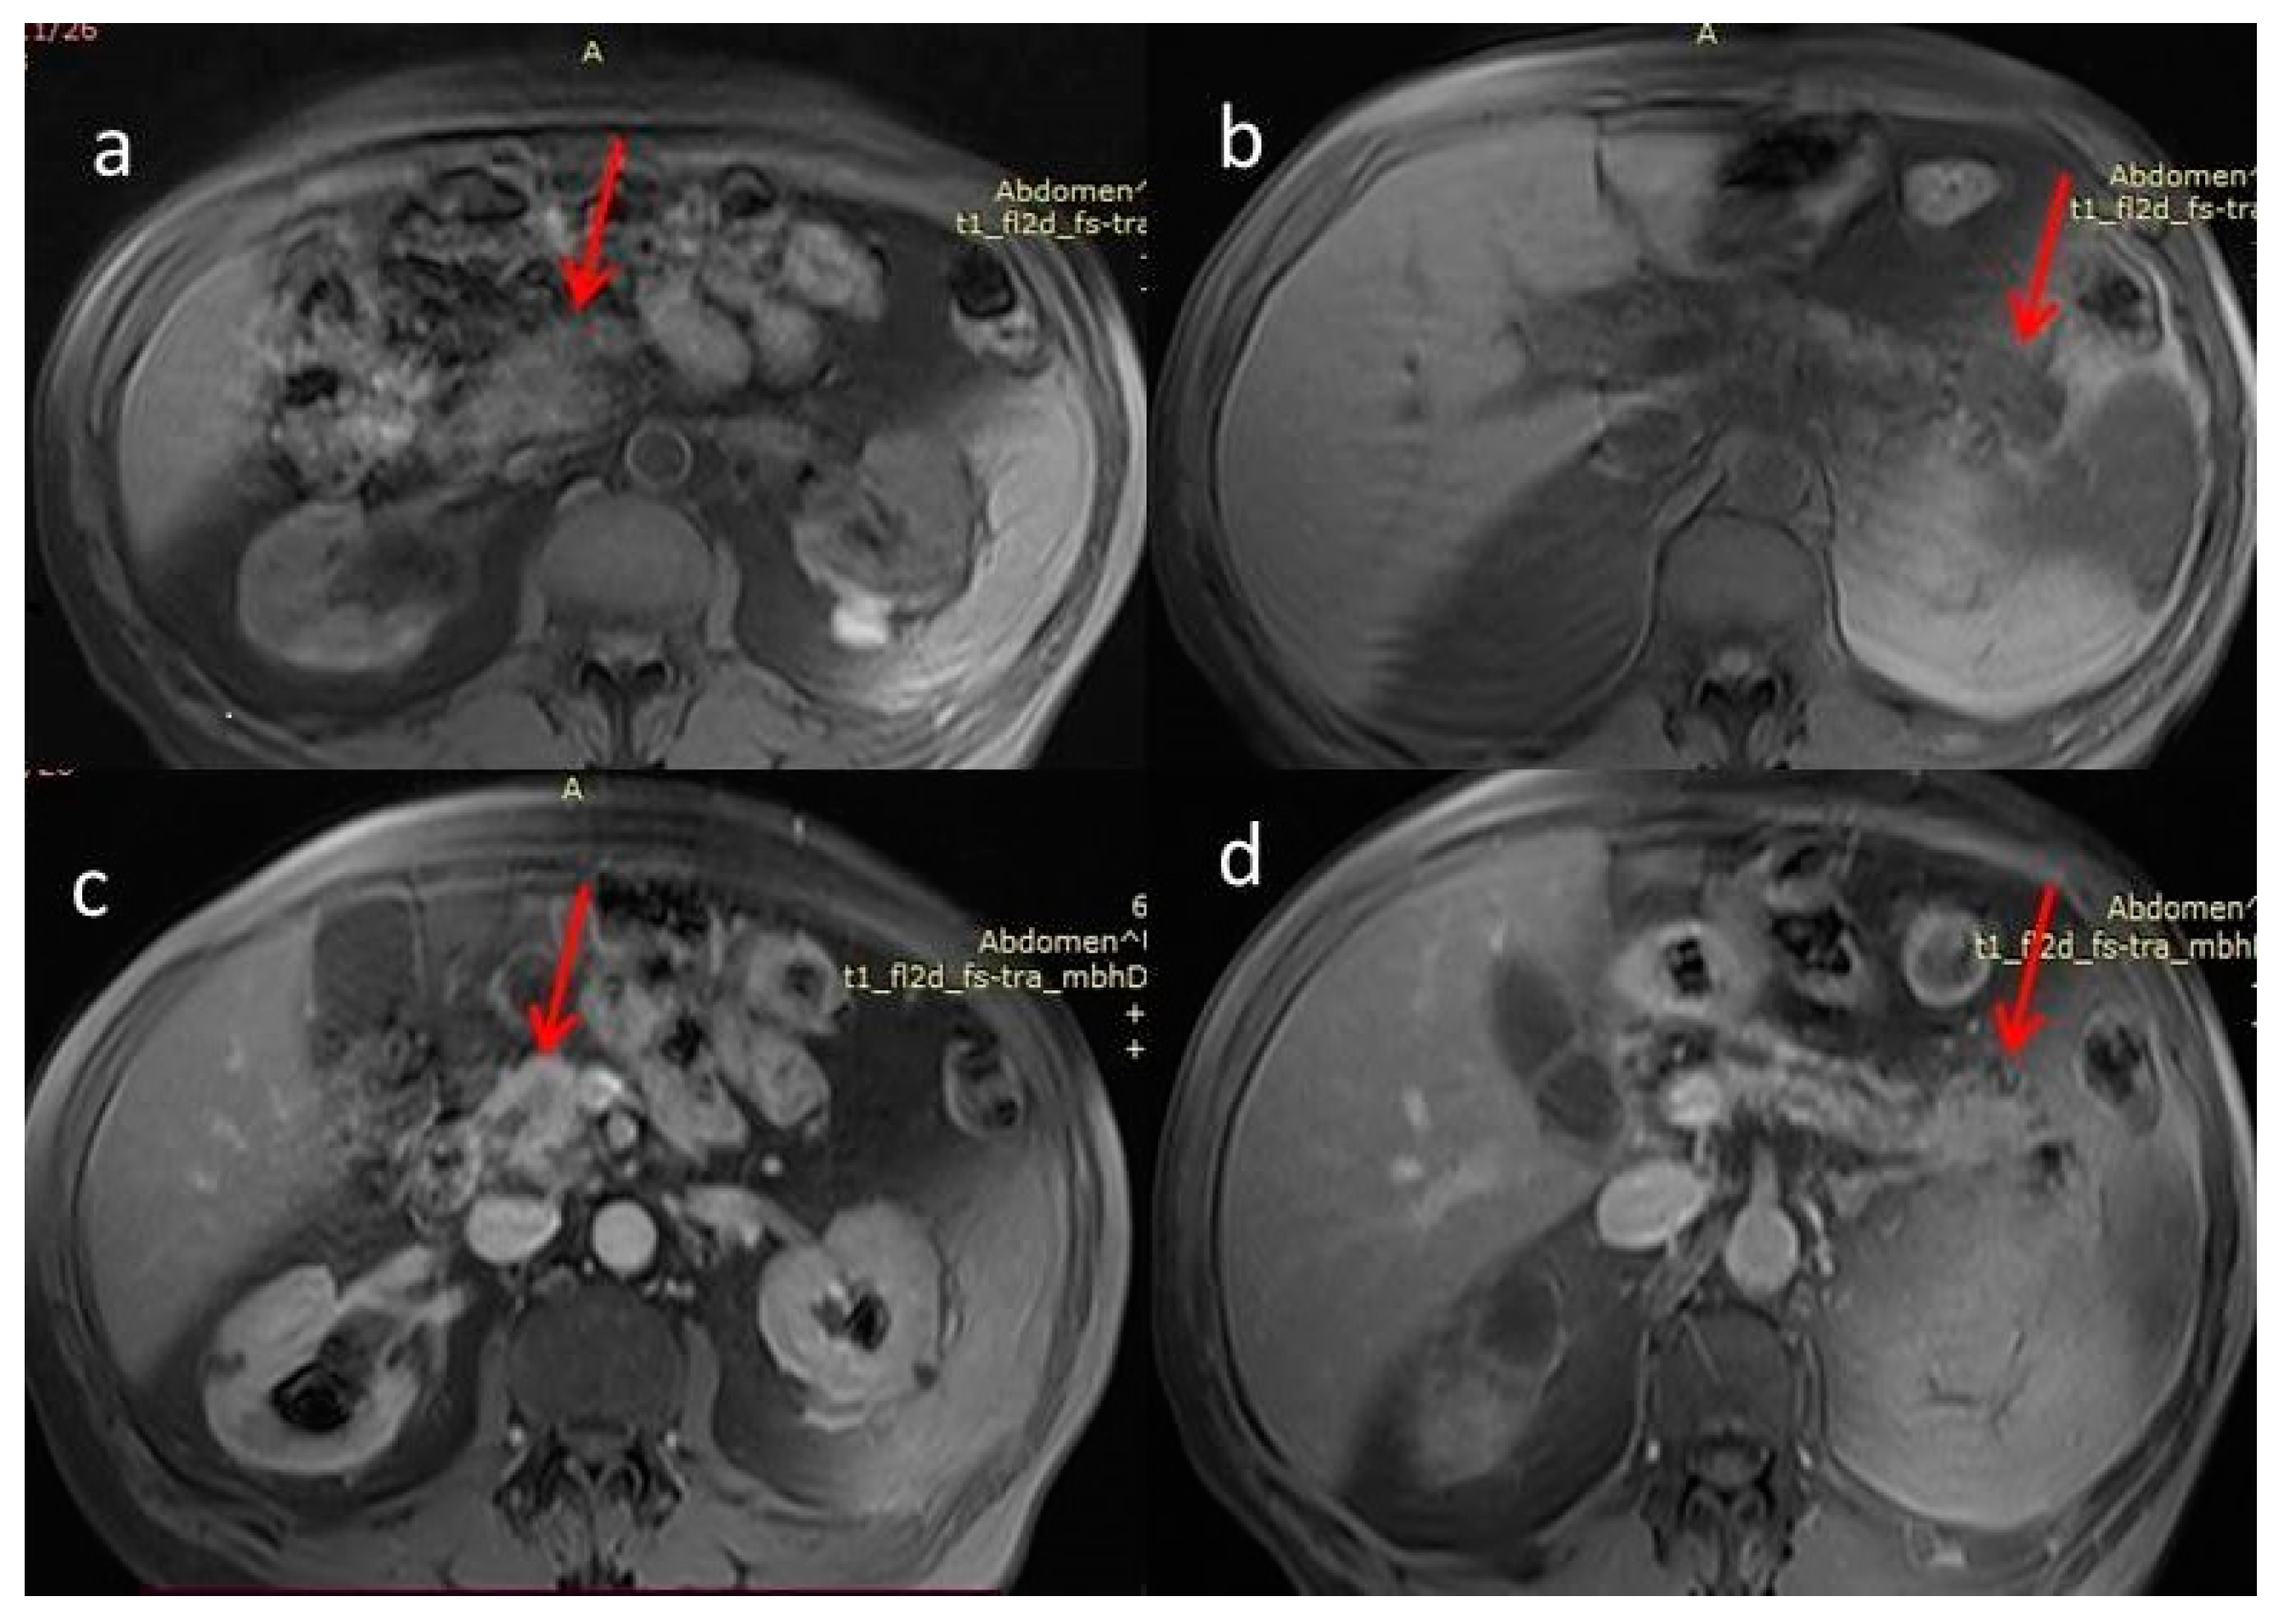

For further investigation and a better depiction, a contrast-enhanced magnetic resonance imaging/magnetic resonance cholangiopancreatography (MRI/MRCP) was performed, which showed an ill-defined hypointense lesion in the head of the pancreas with restricted diffusion. The main pancreatic duct (MPD) and its branch ducts appeared significantly dilated, mainly in the pancreatic head and tail (Figure 3 and Figure 4). In addition to this, MRI/MRCP demonstrated the presence of IPMN in the pancreatic parenchyma (Figure 5).

Figure 4.

(a,b) Magnetic resonance imaging fat-suppressed T1 weighted image (MRI T1WI FS). Hypointense masses. (c,d) Magnetic resonance imaging with fat-suppressed post-Gadolinium T1 (MRI T1GD FS). Hypoenhancement of the masses compared to the normal pancreas (red arrows).